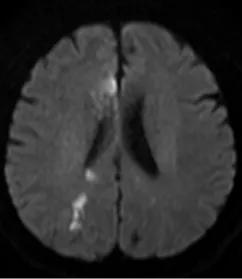

经过一段时间的甲泼尼龙治疗后,患者的症状获得显著改善。再次复查“磁共振高分辨颅内血管壁成像”时,结果显示患者脑内多处血管壁的强化程度显著减低,右侧大脑前动脉的管壁强化也明显减少,表明治疗取得了积极的效果。

激素治疗后

激素治疗后,脑内动脉强化范围减小、强化程度减低,患者症状显著改善。